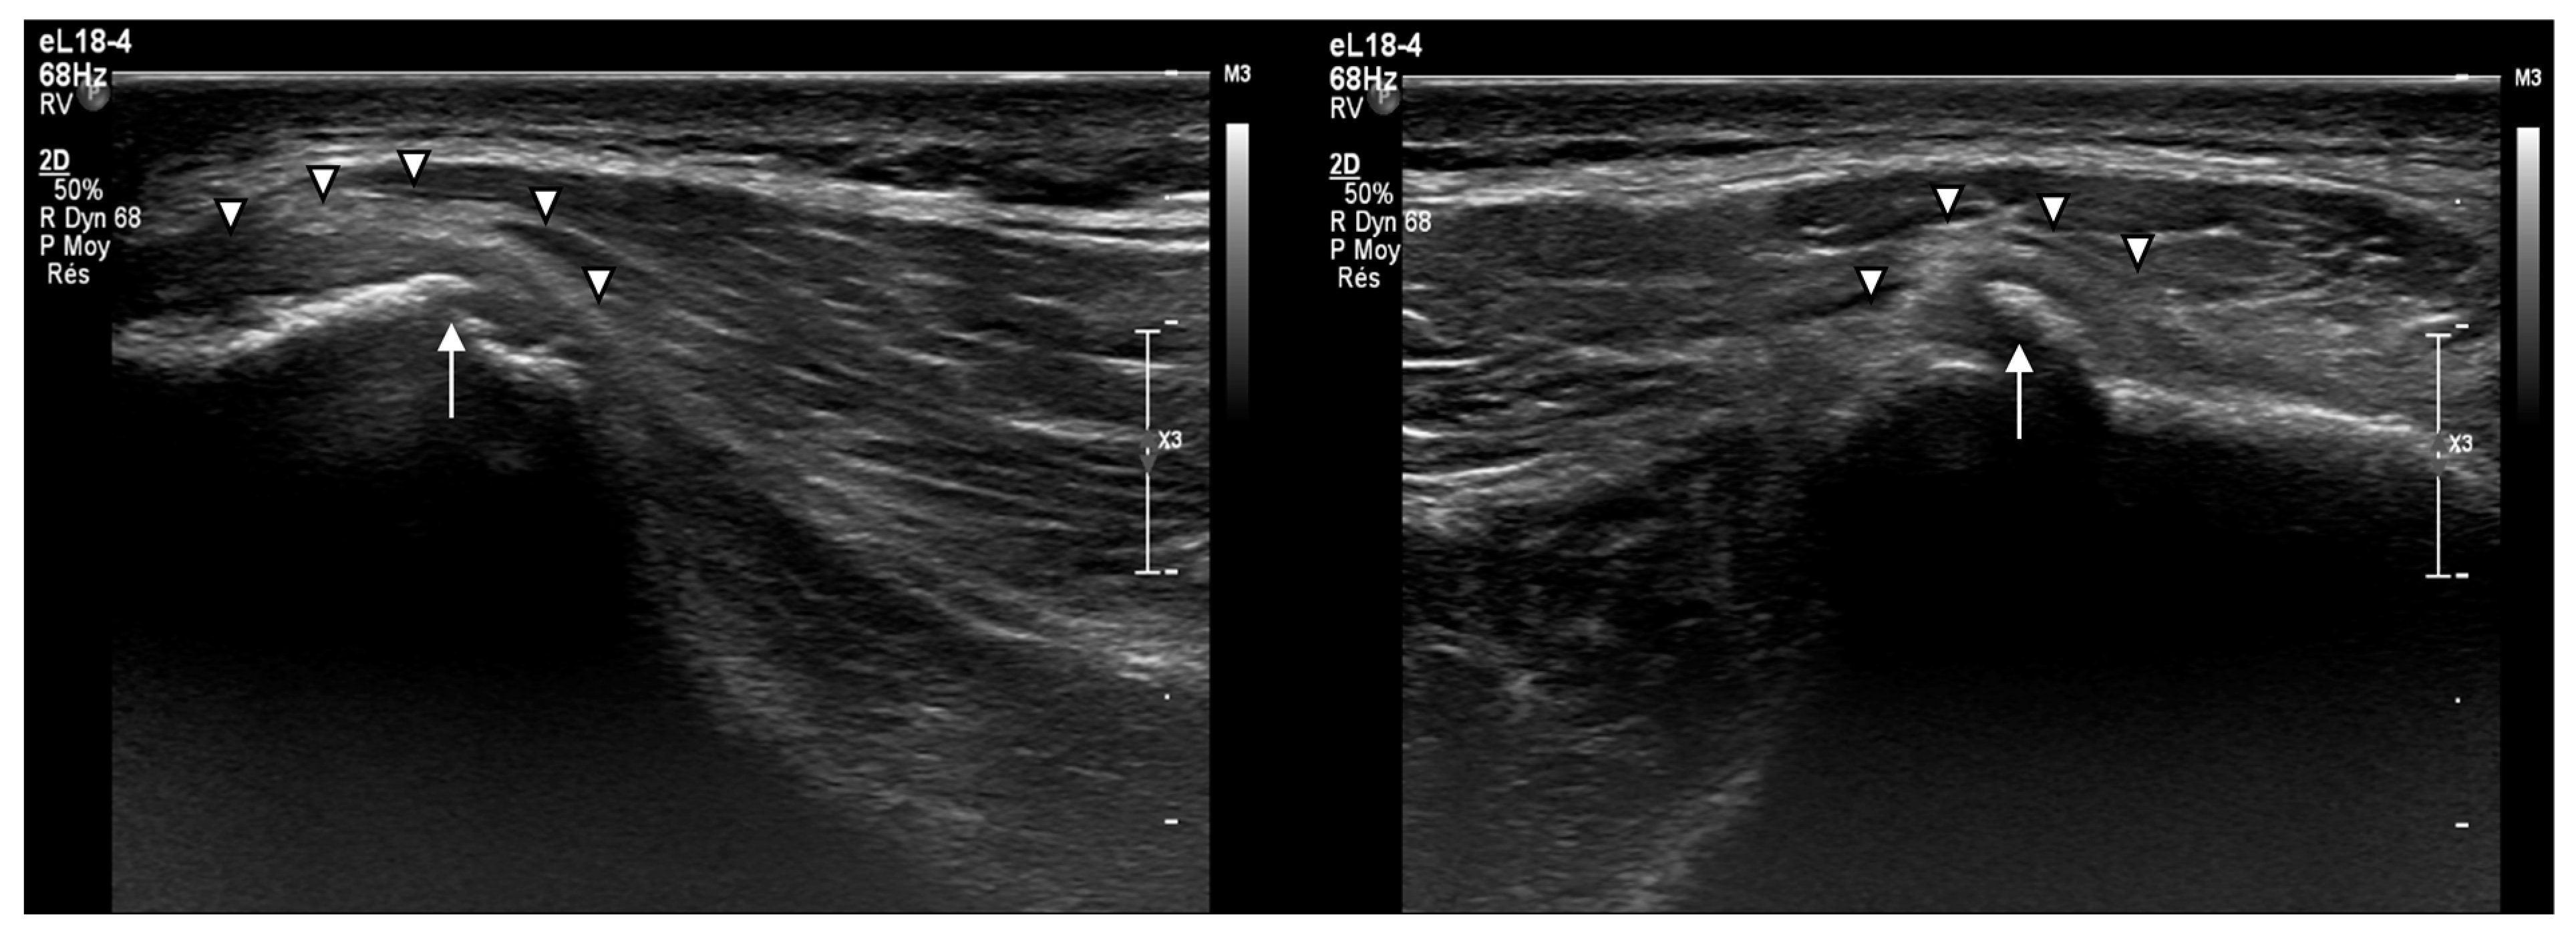

- Subperiosteal hematoma at the posterior iliac crest;

- A 20–25 mm detachment of the gluteus maximus;

- Partial involvement of the gluteus medius.

- Persistent cortical irregularities, including calcifications and periosteal thickening, on long-term follow-up.